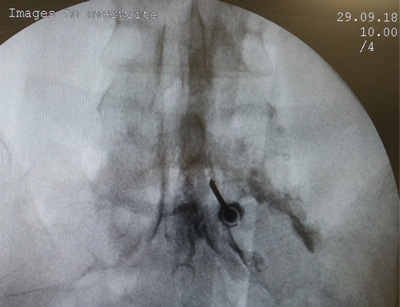

Tablas y Figuras

Figura 2